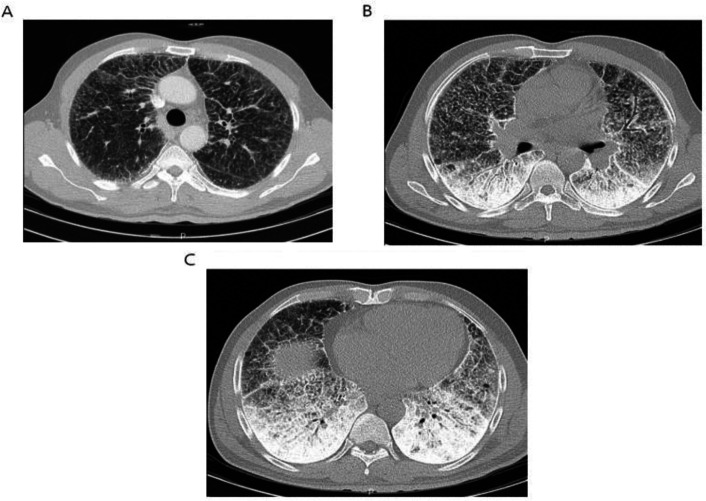

Case presentation: Herein, we have reported a 50-year-old male presented with recent sore throat, fever, and sweating. Radiological findings revealed bilateral micronodular pattern with diffuse ground glass attenuation in lower regions. Subsequent histologic examination of lung biopsy confirmed intra-alveolar accumulation of calculi and the diagnosis of PAM. In addition, we reviewed the literature narratively to clarify different aspects of PAM.

Conclusion: In this paper, we presented a sporadic case of PAM which was suspected with chest x-ray and confirmed by HRCT and trans-bronchial lung biopsy. We hope that it can help clinicians to be more aware of this condition and make proper diagnosis.

Abstract Image